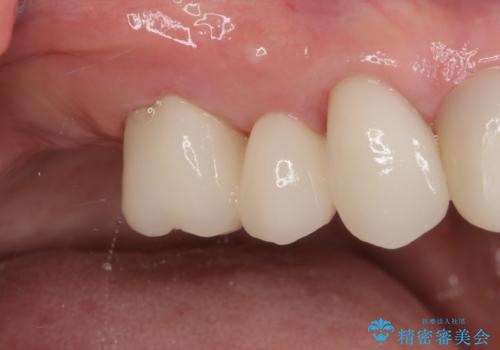

歯の欠損を放置 オールセラミックブリッジによる補綴治療

下顎には抜歯が必要な歯があったため、抜歯後に治癒を待ち、上顎とともにオールセラミックブリッジにて補綴治療を行うこととしました。

治療開始の日に欠損部も含めて仮歯が装着され、今までの不具合や不快感があっという間に改善されました。